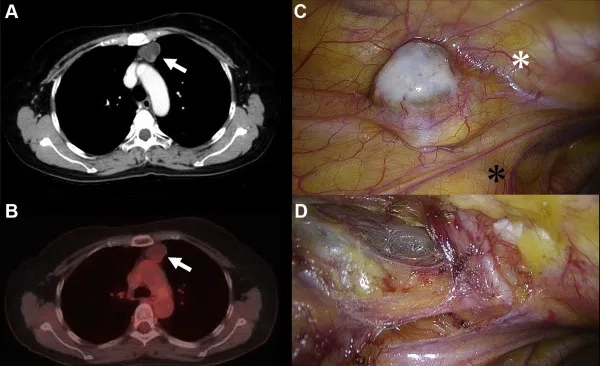

Detailed images of ovarian cancer